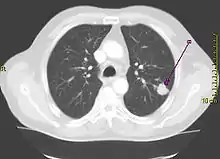

![]() Рентгенограма органів грудної порожнини: рак легені - затемнення з нерівним та нечітким контуром (позначено стрілкою). Рентгенограма органів грудної порожнини: рак легені - затемнення з нерівним та нечітким контуром (позначено стрілкою). | |

Рентгенограма грудної клітини — це один з перших кроків, які необхідно зробити, якщо пацієнт повідомляє про симптоми, які можуть вказувати на рак легень. Рентгенограма може виявити видиму пухлину, розширення середостіння (що може вказувати на поширення у лімфатичні вузли), ателектаз (колапс), консолідацію (пневмонію) або плеврит.[5] Для отримання більш докладної інформації проти тип та ступінь захворювання зазвичай використовується комп'ютерна томографія. Пробу пухлини для гістопатології зазвичай беруть за допомогою бронхоскопії або біопсії під контролем КТ.[13]

На рентгенограмі грудної клітини рак легень часто проявляється як солітарний легеневий вузол. Однак диференційна діагностика цього захворювання може зайняти багато часу. Багато інших захворювань може мати такі ж ознаки, в тому числі туберкульоз, грибкові інфекції, метастатичний рак або пневмосклероз. Менш поширеними причинами утворення солітарного легеневого вузла є гамартома, бронхогенна кіста, аденома, артеріовенозна мальформація, легенева секвестрація, ревматоїдні вузли, гранулематоз Вегенера або лімфома.[45] Рак легень можна також виявити випадково, знайшовши солітарний легеневий вузол на рентгенограмі грудної клітини або комп'ютерній томограмі, які були зроблені з інших причин.[46] Остаточний діагноз ставлять на основі гістологічного дослідження підозрілих тканин з огляду на клінічні та рентгенологічні ознаки.[3]